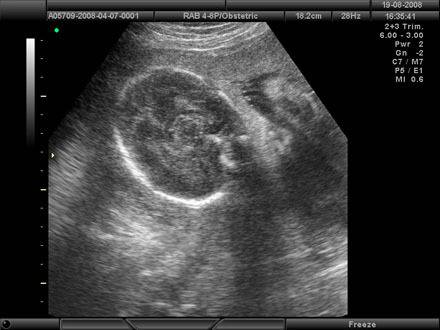

Обикновено, ако в резултат на теста бременната жена покаже високи нива на AFP, това показва възможен риск от спина бифида или друг дефект на невралната тръба. В такъв случай нейният лекар ще препоръча детайлен преглед с ултразвук, чрез който ще изследва плода, включително неговият череп и гръбначен стълб. В допълнение, ултразвука може да потвърди възрастта на плода и дали жената е бременна с близнаци. Също така, лекарят може да препоръча амниоцентеза, която представлява изтегляне на околоплодна течност от матката, за по-нататъчни изследвания.

Ако резултатът от Скрининговият тест покаже ниски нива на AFP и естриол и вискоки нива на hCG и инхибин-А, тя има повишен риск от раждане на бебе със Синдром на Даун. Следващата стъпка често е ултразвук, за да се установи термина и за да се прегледа за някои очевидни  аномалии. За съжаление, ултразвука не е много добър тест за установяване на Синдром на Даун. По тази причина, на бременните жени се предлага амниоцентеза, за да може да се направи хромозомен тест на феталните клетки открити в околоплодната течност.